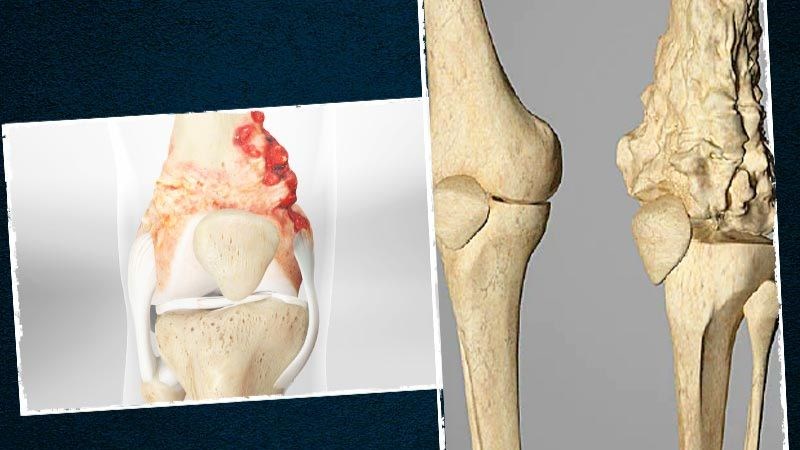

Sarcoma xương (Osteosarcoma)

Sarcoma xương là một loại ung thư xương xuất hiện trong các tế bào hình thành xương. Sarcoma xương thường được tìm thấy ở các xương dài, phổ biến nhất là ở chân, ít gặp hơn là ở cánh tay hoặc ở bất kỳ xương nào trong cơ thể. Trong những trường hợp rất hiếm, nó xảy ra ở cả mô mềm bên ngoài xương.

Độ tuổi thường gặp: Sarcoma xương thường có xu hướng xảy ra ở thanh thiếu niên, nhưng nó cũng có thể xảy ra ở trẻ nhỏ và người lớn tuổi.

Sarcoma xương là một loại ung thư xương xuất hiện trong các tế bào hình thành xương